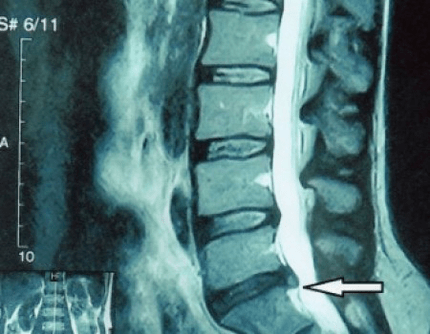

Dado que os propios discos só se poden ver mediante TC ou resonancia magnética, a resonancia magnética e a tomografía computarizada de raios X están indicadas para aclarar a estrutura interna da cartilaxe e formacións como protuberancias e hernias. Así, coa axuda destes métodos, faise un diagnóstico con precisión e o resultado da tomografía é unha indicación, e mesmo unha guía tópica, para o tratamento cirúrxico dunha hernia no departamento de neurocirurxía.

- se tes unha hernia, debes monitorala dinámicamente, facer resonancias magnéticas regulares, evitar o aumento do seu tamaño ou realizar un tratamento cirúrxico moderno mínimamente invasivo, xa que, sen excepción, todos os métodos conservadores para tratar a exacerbación da osteocondrose deixan a hernia no seu lugar e só eliminan os síntomas temporais: inflamación, dor, tiroteo e espasmos musculares.

É recomendable que cada paciente, despois da progresión dos síntomas, ante a presenza de complicacións, se someta a unha resonancia magnética e consulte a un neurocirurxián. As operacións modernas mínimamente invasivas permiten extirpar con seguridade hernias bastante grandes, sen hospitalización prolongada, sen ser obrigado a deitarse durante varios días, sen comprometer a calidade de vida, xa que se realizan mediante tecnoloxía moderna de videoendoscopia, radiofrecuencia, láser ou plasma frío. Pode evaporar parte do núcleo e baixar a presión, reducindo o risco de sufrir unha hernia. E podes eliminar o defecto radicalmente, é dicir, desfacendo del por completo.